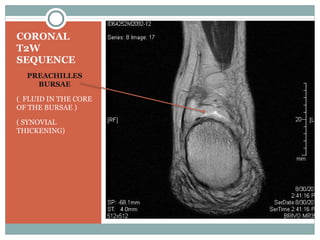

CORONAL

T2W

SEQUENCE

PREACHILLES

BURSAE

( FLUID IN THE CORE

OF THE BURSAE )

( SYNOVIAL

THICKENING)